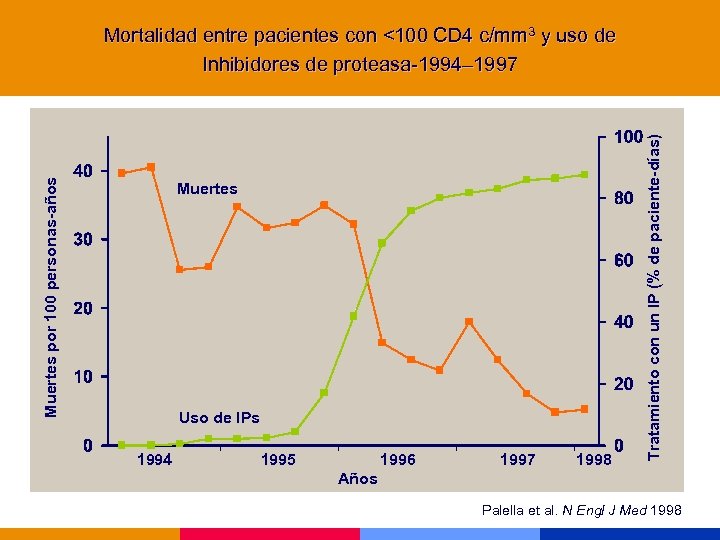

Muertes Uso de IPs 1994 1995 1996 1997 1998 Tratamiento con un IP (% de paciente-días) Muertes por 100 personas-años Mortalidad entre pacientes con <100 CD 4 c/mm 3 y uso de Inhibidores de proteasa-1994– 1997 Años Palella et al. N Engl J Med 1998

Muertes Uso de IPs 1994 1995 1996 1997 1998 Tratamiento con un IP (% de paciente-días) Muertes por 100 personas-años Mortalidad entre pacientes con <100 CD 4 c/mm 3 y uso de Inhibidores de proteasa-1994– 1997 Años Palella et al. N Engl J Med 1998